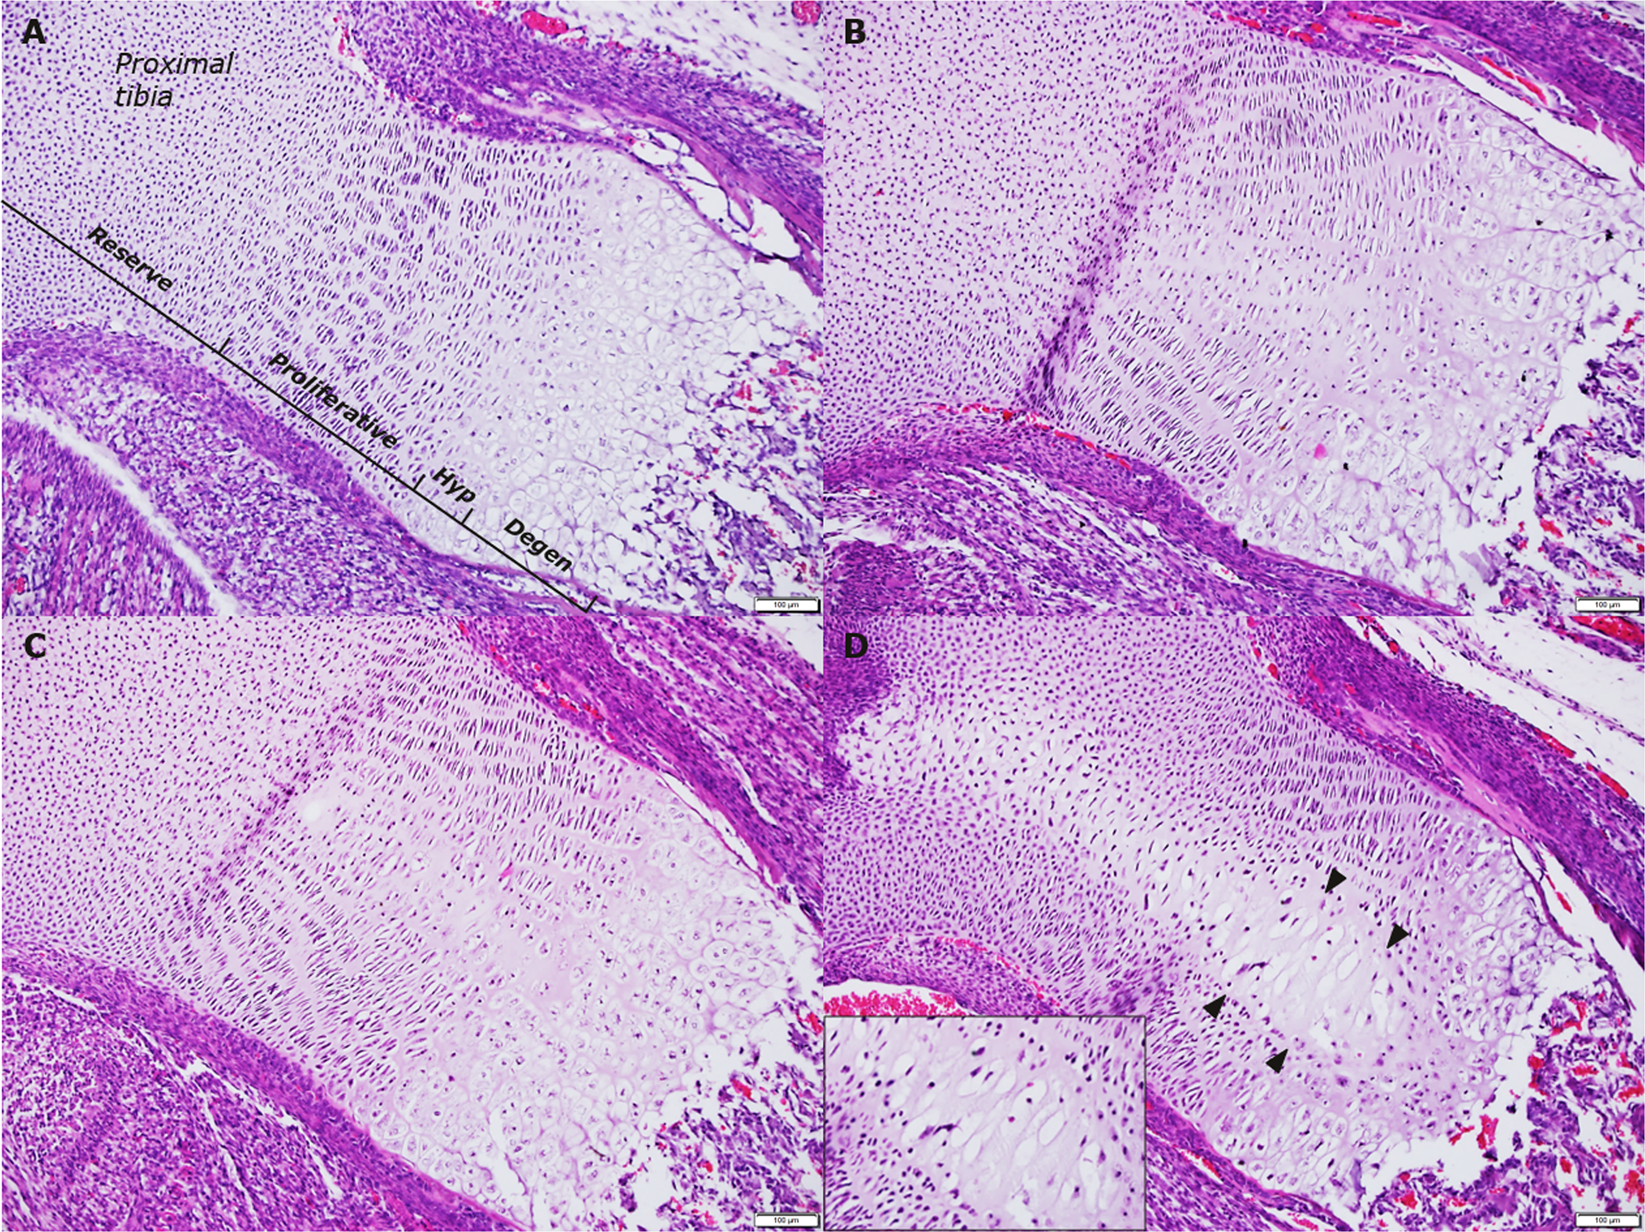

Figure 1

Representative examples of histopathologic changes in foetal tibial growth plates resulting from HI-infusion throughout gestation. (A) Grade 0, no changes. (B) Grade 1, minimal morphological changes centrally, involving all zones except reserve zone. (C) Grade 2, moderate morphological changes centrally, involving all zones except reserve zone. (D) Grade 3, severe morphological changes centrally (arrowheads), involving all zones, with loss of columnar organisation of chondrocytes, the few remaining chondrocytes appearing hypertrophic with pyknotic nuclei (insert). Degen, degenerative; Hyp, hypertrophic. Magnification: x100; insert x200.